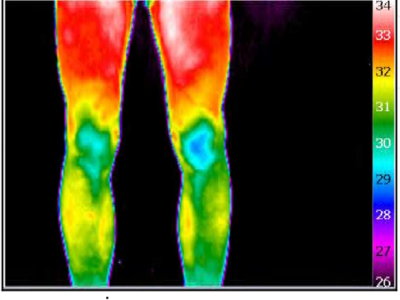

- Application of Infrared Thermal Imaging in Medical DiagnosisInfrared thermal imaging technology has a wide range of medical applications, especially in the fields of rheumatology, neurology, oncology, physical therapy and sports medicine. The following are some applications of infrared thermal imaging in medical diagnosis.Apr 28,2022

- What Are the Applications of Infrared Thermal Imaging Technology in the Medical Field?You can read this article to learn more about the application of infrared thermal imaging technology in the medical field.Jan 11,2022

- How is Infrared Thermal Imaging Technology Applied in the Field of Sports Rehabilitation?This article will specifically share the specific application of infrared thermal imaging technology in the field of sports rehabilitation so that everyone can better understand the characteristics and advantages of infrared imaging technology.Dec 27,2021

- Application and Research of Infrared Thermal Imaging Technology in Biometric DetectionThis article specifically shares the specific applications of infrared thermal imaging technology in human and veterinary medicine, ecology, zoology, and other fields for your reference.Feb 14,2022